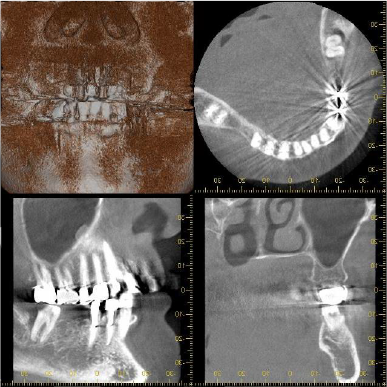

CT所見

ほぼ骨内には埋入できましたが、骨の厚みが足りないため、人工骨を移植し縫合しました。